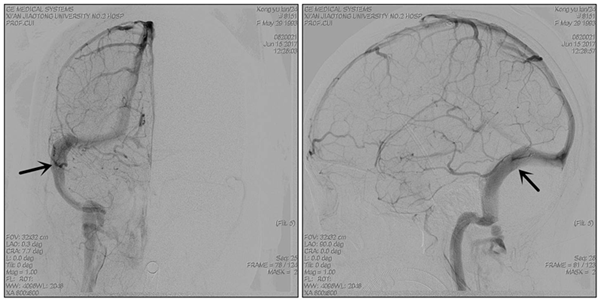

图片2_副本.png

术后造影显示静脉窦狭窄消失

经过5天的术前抗血小板治疗,于2017年6月10日成功为患者施行了静脉窦狭窄支架成形术,术中顺利,即刻测量狭窄远、近端压力差为:0。术后患者头痛完全缓解,视力也开始慢慢恢复、癫痫发作完全消失,3日后腰穿颅内压下降为75mmH2O,转当地医院眼科继续治疗。